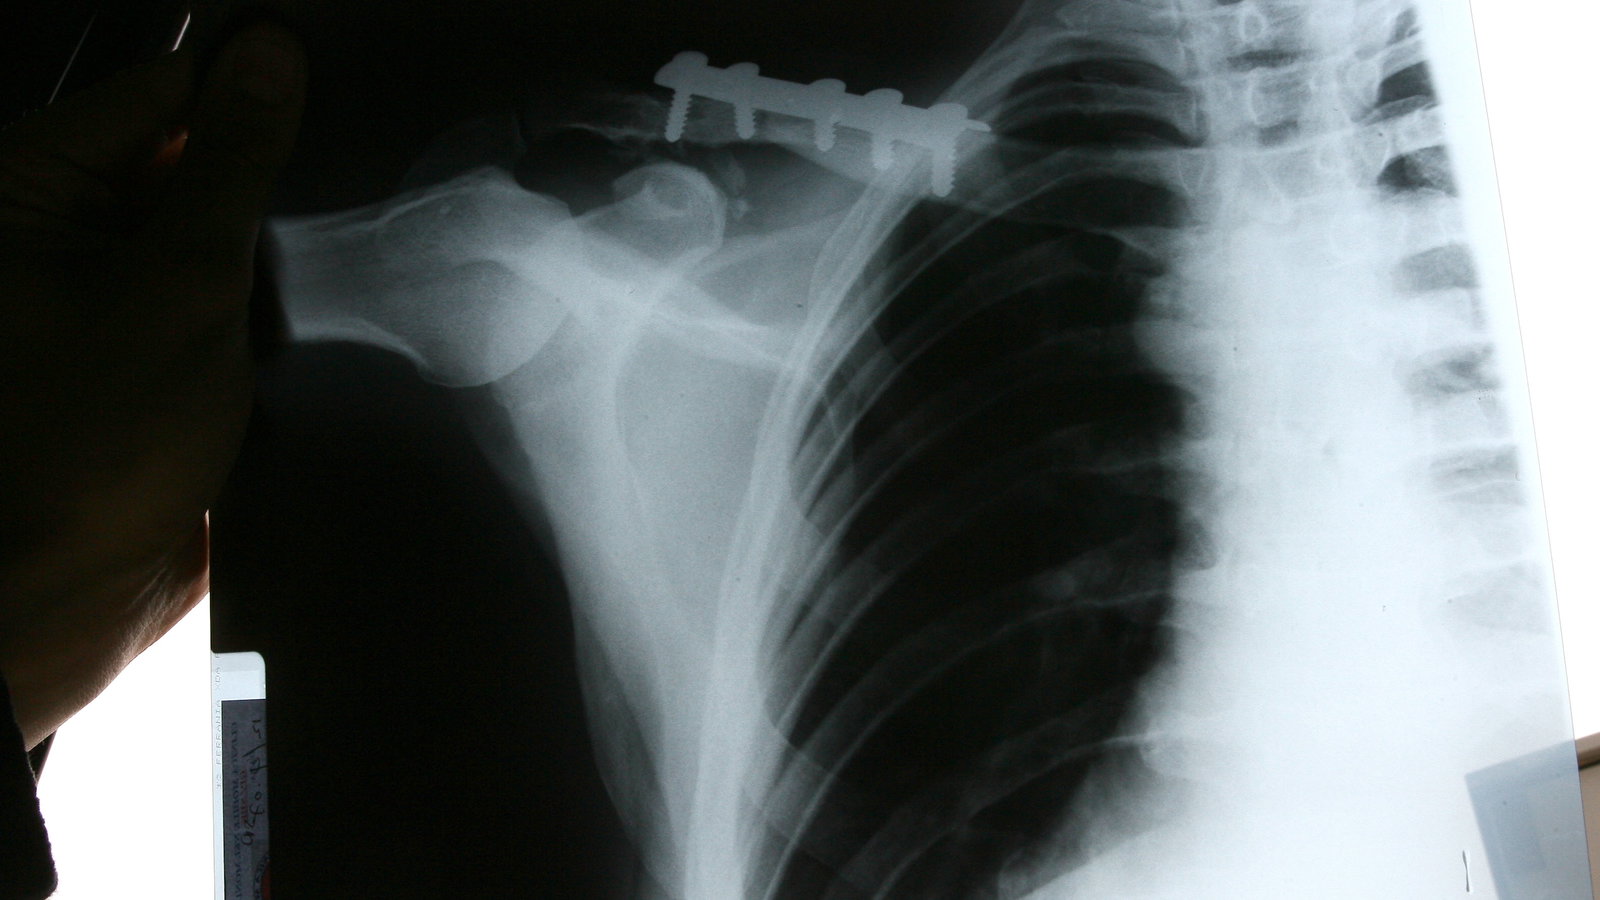

Ouch! These x-rays show the latest metalwork inserted into the fractured collarbones of Yamaha World Supersport team-mates Broc Parkes (top and middle pictures) and Kevin Curtain after both were injured, at the same corner, during Friday free practice at Donington Park two weeks ago.